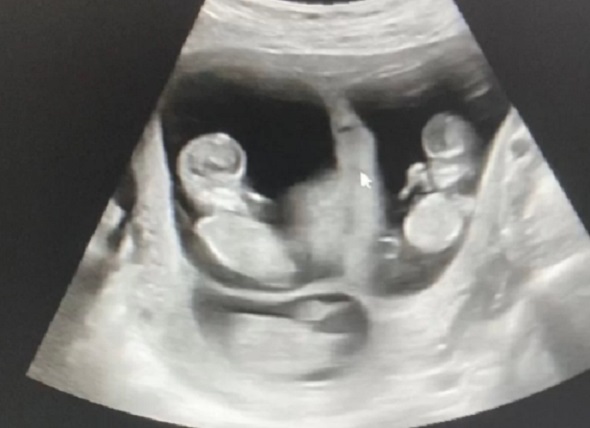

A gravação mostra o médico conversando com Carolina Rodrigues, de 29 anos, e Natan Reis durante o exame. Carolina, que já é mãe de duas filhas, conta ao médico que não estava tentando engravidar e estava tomando anticoncepcional. Durante o ultrassom, o médico faz suspense e, inicialmente, anuncia a chegada de gêmeos.

No entanto, o médico guarda a maior surpresa para o final: “Mas eu fiquei sabendo que teve briga lá no céu. Porque, na verdade, três escolheram, três escolheram a mamãe.” Neste momento, Natan desmaia e cai no chão. O médico encerra o vídeo explicando o ocorrido: “Pessoal, eu tive que encerrar o vídeo. O pai acabou caindo ali na hora que a gente revelou que eram [três]. Foi bem inesperado. Mas foi isso, vamos acompanhar essa gestação toda”, conclui.